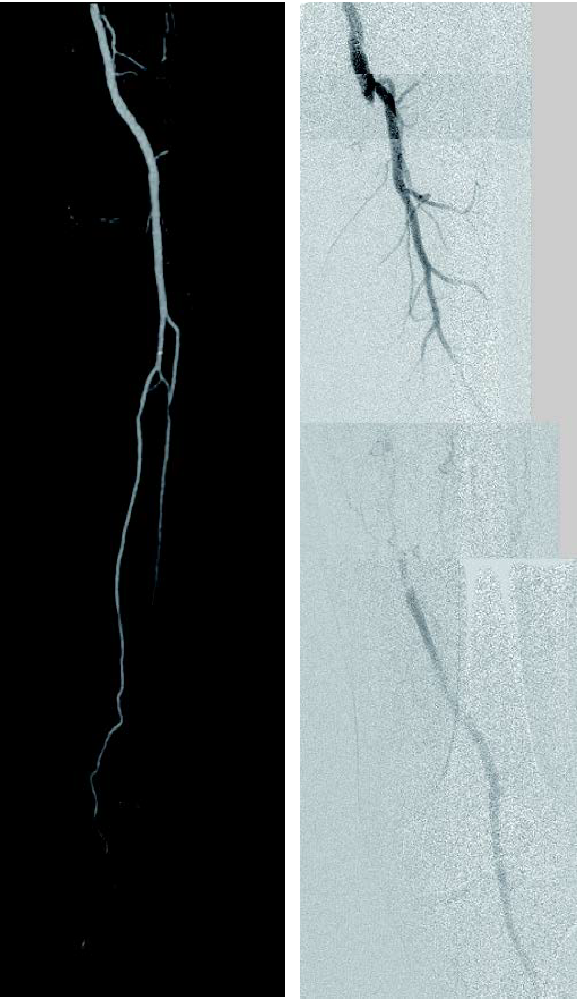

- 対象病変部位(図1): 左 SFA 閉塞(病変長約22 cm)

図1:術前

- IVUSにて遠位部のヘルシーな部分をマーキングし、バイアバーン® ステントグラフト径6.0/長250 mm を留置(図2)。

- 造影上は良好な血流改善を得られたが、IVUSではSFA起始部にプラーク残存を認めた(図3)。

- プラークをフルカバーするため、SFA起始部にバイアバーン® ステントグラフト径6.0/長50 mmを追加留置(図4)。

- 径6.0/長150 mm高圧バルーンにて高圧拡張を追加し、DFAの血流も問題がないことを確認して手技終了(図5)。